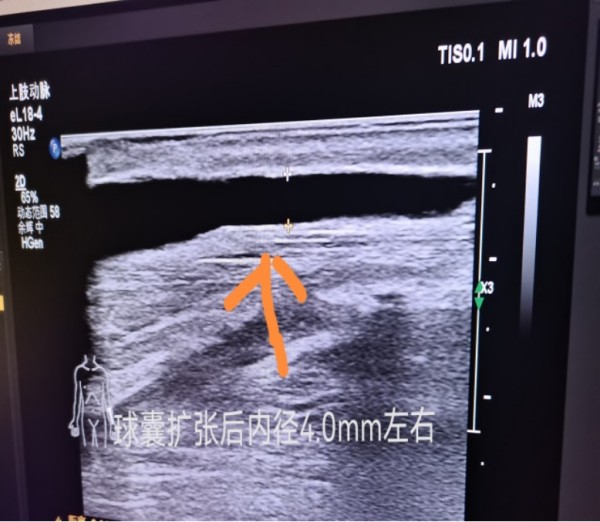

患者周某,老年女性,既往有肾功能异常病史3+年,已维持性血液透析治疗8月,合并糖尿病、糖尿病视网膜病变、冠心病、高血压等多种基础疾病。该患者近2月来透析流量差,穿刺困难,经过彩超检查发现左腕部动静脉内瘘流出段瘘静脉狭窄,桡动脉管径细,有指征行球囊扩张术,如果不进行手术,可能导致透析不充分,透析质量越来越差,最终并发各种严重并发症,故解决患者血管通路问题迫在眉睫。经过与患者及家属详细沟通,同意行球囊扩张术。现已成功为该患者实施了左腕部动静脉内瘘狭窄段球囊扩张术,为患者重新开通了生命线。术后触诊检查震颤明显,听诊杂音响亮,手术取得圆满成功。